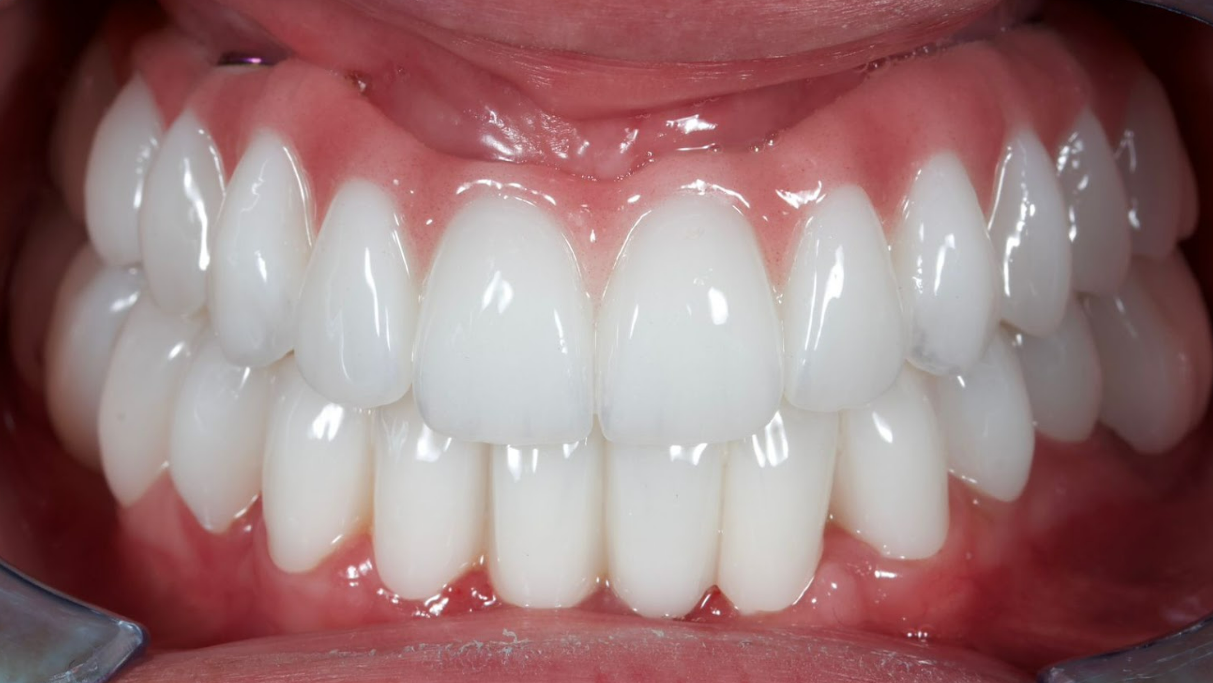

Next, using CAD/CAM technologies, a fixed, full-contour zirconia bridge was manufactured, designed for screw retention on titanium sleeves.

The following images show the final treatment result. The patient expressed complete satisfaction with both the functional outcome and the aesthetic aspects of the restoration.